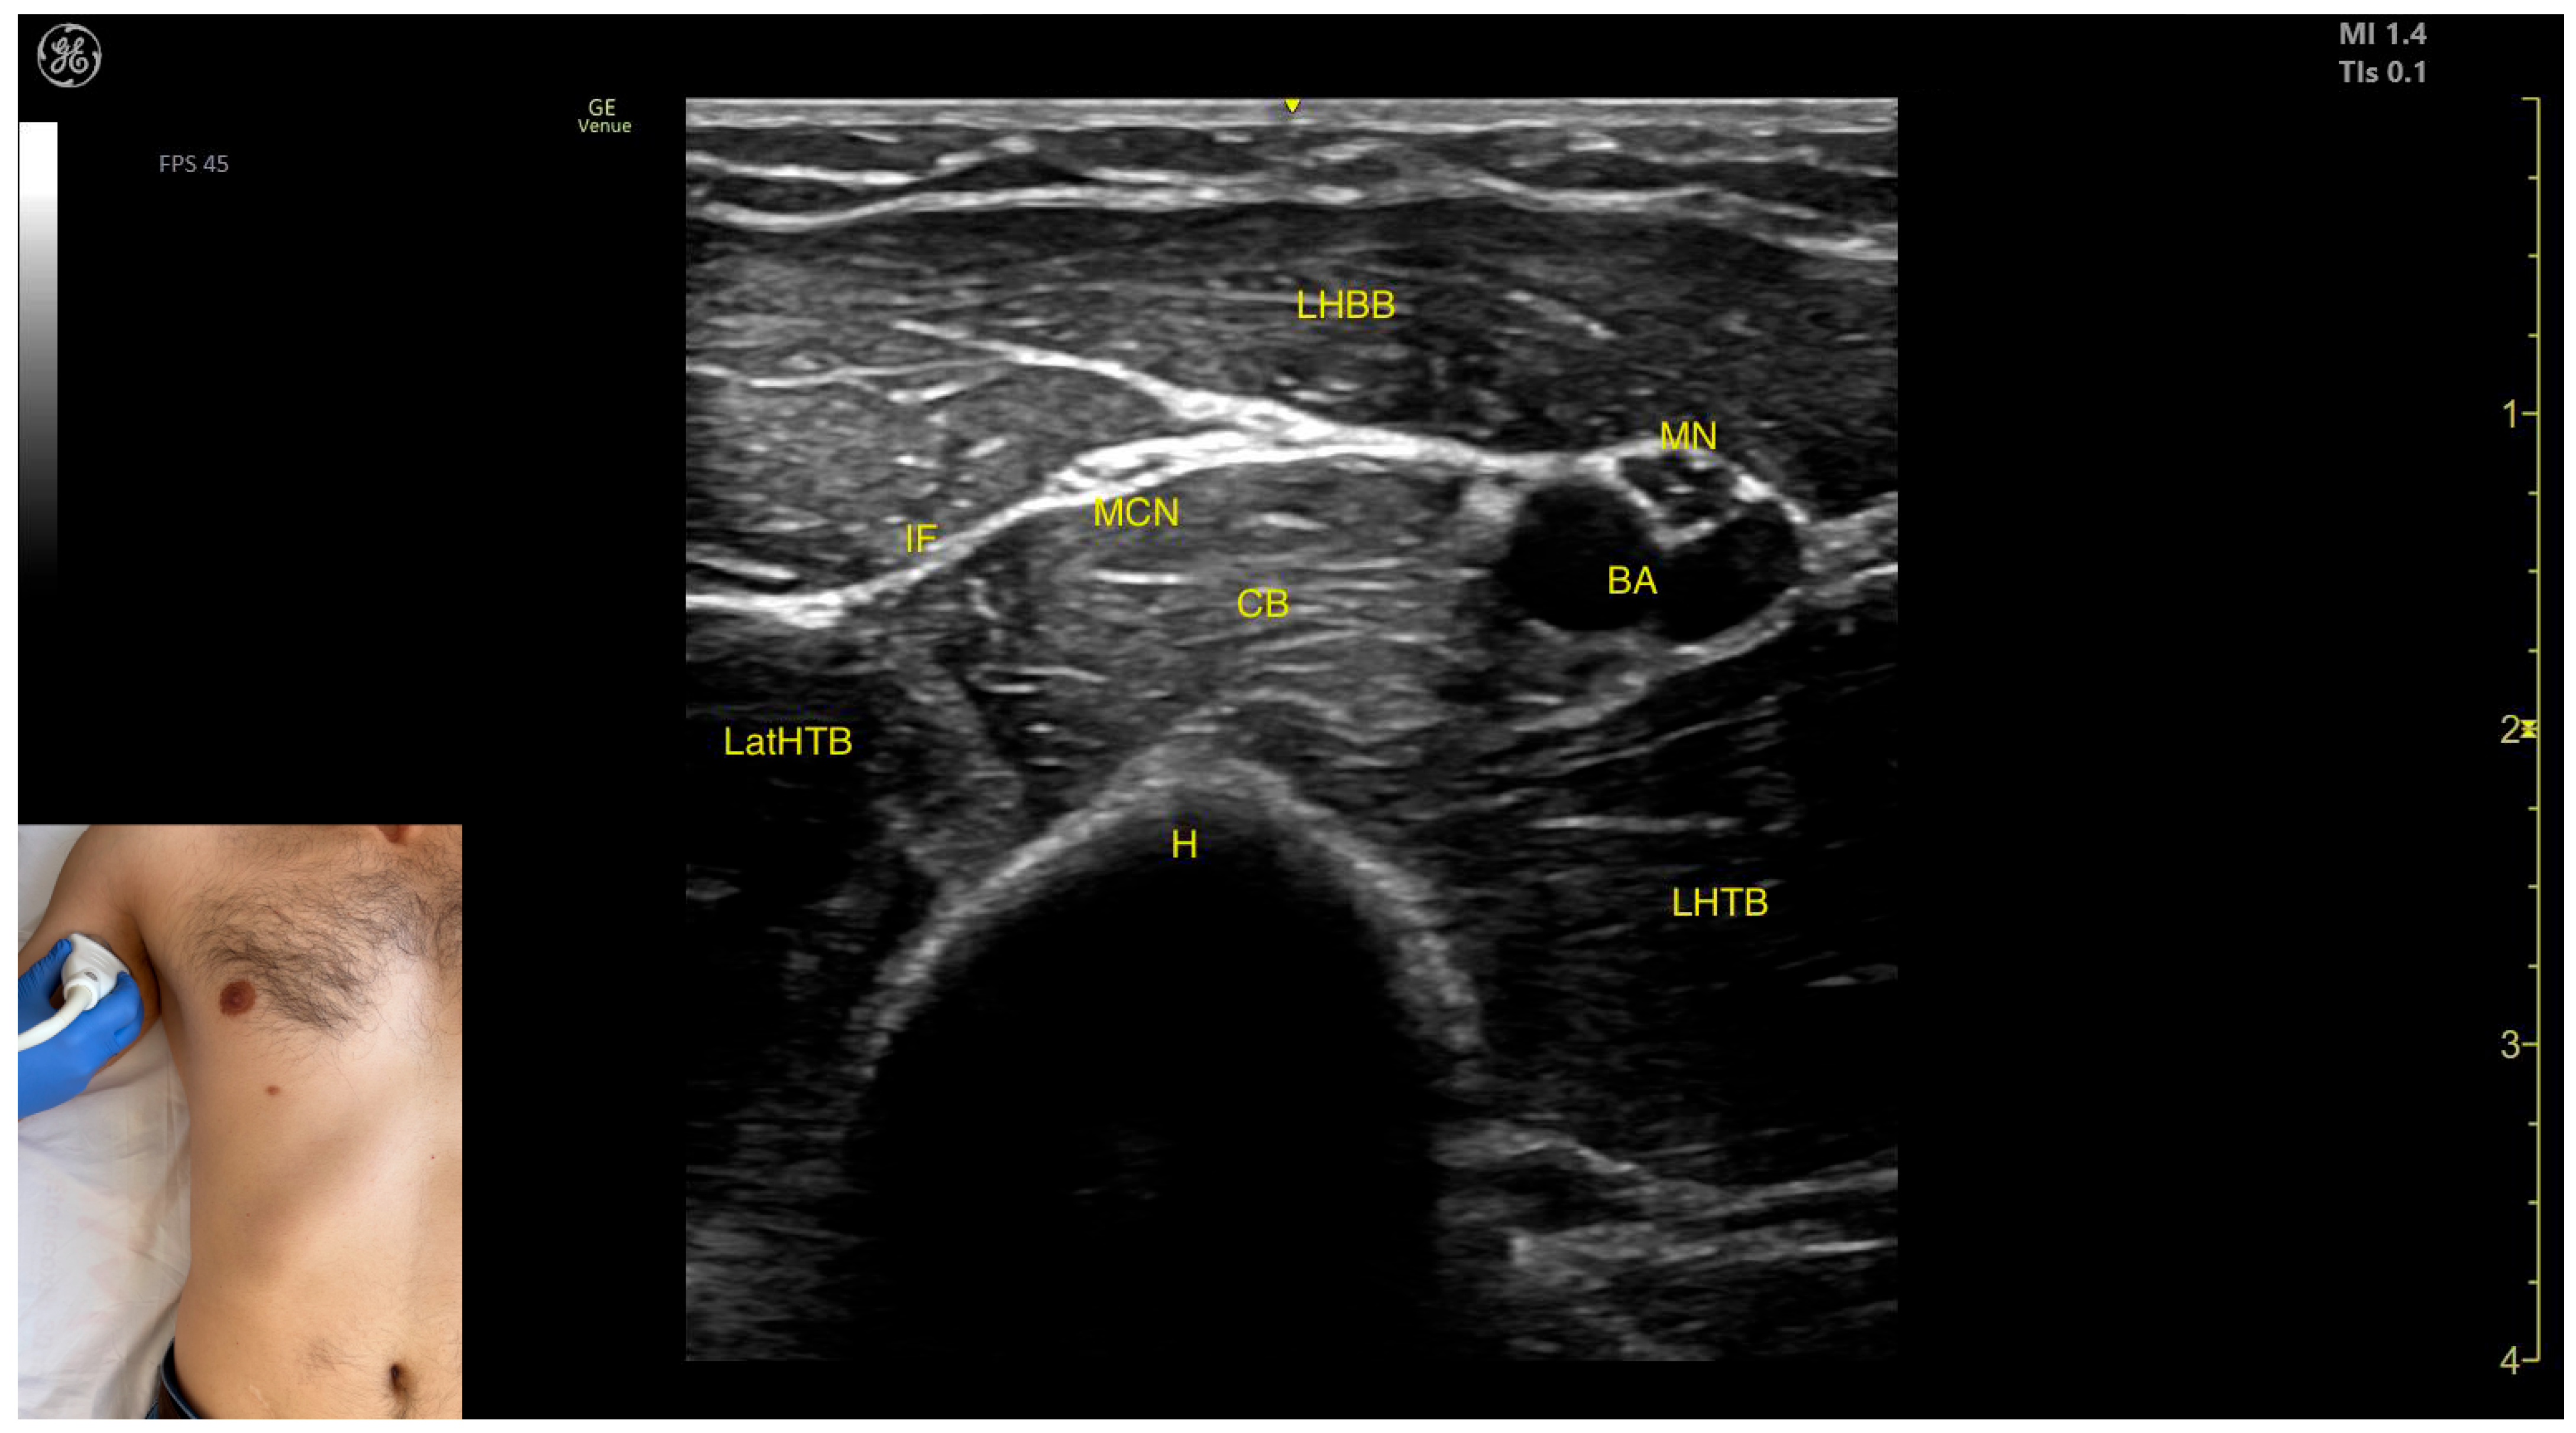

- Muscle morphology: The TB has three heads—long, medial, and lateral—each of which can be approached individually. These three heads are separated by intramuscular fasciae:- 1.

- Long head (LHTB): Located superficial to the cortical bone of the humerus.

- Medial head (MHTB): Found medial to the humeral cortex.

- Lateral head (LatHTB): Situated between the long and medial heads.

- Innervation and vascular supply: In the medial portion of the TB, the neurovascular bundle is observed, consisting of three nerves—median, radial, and ulnar—and two vascular structures, namely the brachial artery with its branches and the brachial vein.

- External fascia: The TB features a pronounced fascia that separates it from the superficial plane during BoNT-A injections.

- Dynamic evaluation: During dynamic evaluation, scanning distally toward the elbow joint reveals a decrease in the size of the long and lateral heads, while the medial head shows an increase in size. Muscle contraction is visible during elbow extension maneuvers, confirming its role in this movement [12,50].